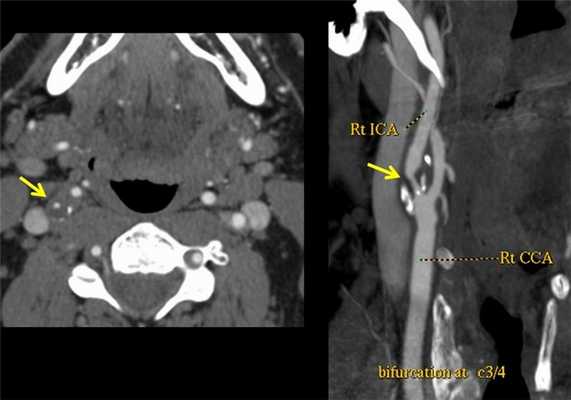

Что выявляет КТ-ангиография. Патологическая извитость внутренних сонных артерий в шейном сегменте (С1). Хорошо виден ход сосудов, можно оценить их диаметр, состояние стенок. Трехмерная (3D) реконструкция сосудов.

![]()

Как выглядит атеросклероз на КТ? Ангиография выявляет сужение правой внутренней сонной артерии атеросклеротической бляшкой. Исследование также позволяет наиболее точно изменить степень сужения сосуда (процент стеноза по методикам ESCT или NASCET). Ангиографию обязательно делать людям с выявленной патологией сосудов на УЗДГ, а также пациентам с повторяющимися инсультами.